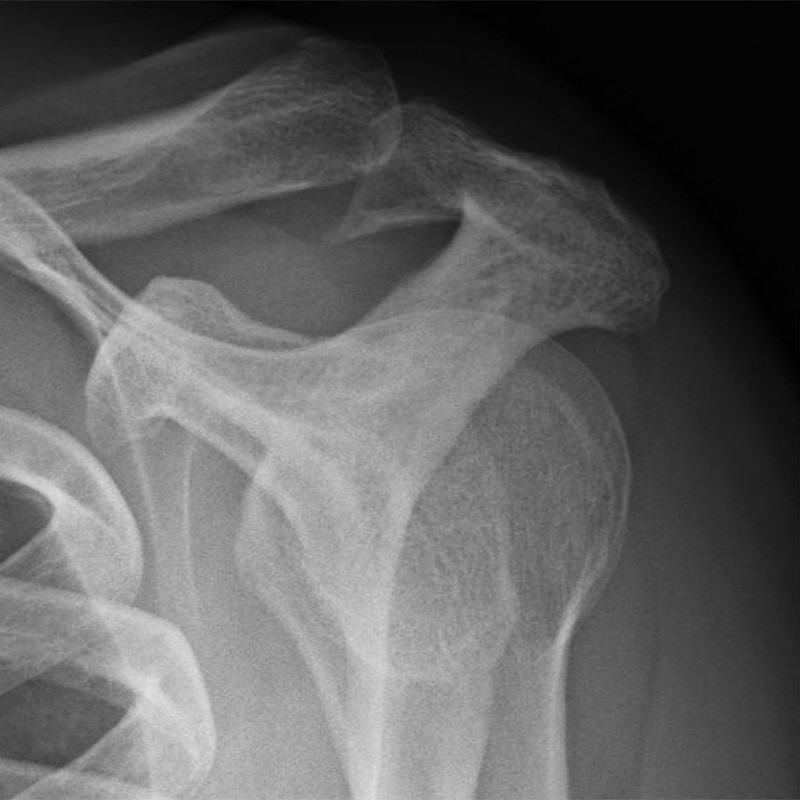

Auf dem Röntgenbild kann man nach der Operation dann die Erweiterung des Raumes auch sehen. Hier ein Beispiel mit einem sehr großen Sporn (linkes Bild) vor und nach der Dekompression (rechtes Bild).

Röntgenbilder der Schulter mit ausgeprägtem Knochensporn: Links vor der Operation und rechts nach der arthroskopischen Abtragung.